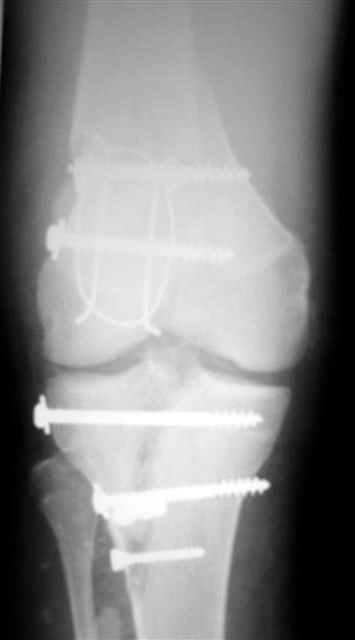

Evgueny Tschekashkin 14 Декабрь 2004, 18:41

Вид раны на сегодня...

4 cутки после травмы.

Спасибо за комментарии. Травма тяжелая с проблематичным прогнозом для функции коленного сустава( изначально травма разгибательного аппарата с последующим частичным некрозом собственной связки надколенника и о обнажением рефиксированного фрагмента бугристости большеберцовой кости, дефектом центрального отдела суставной поверхности большеберцовой кости и медиального отдела капсулы сустава).